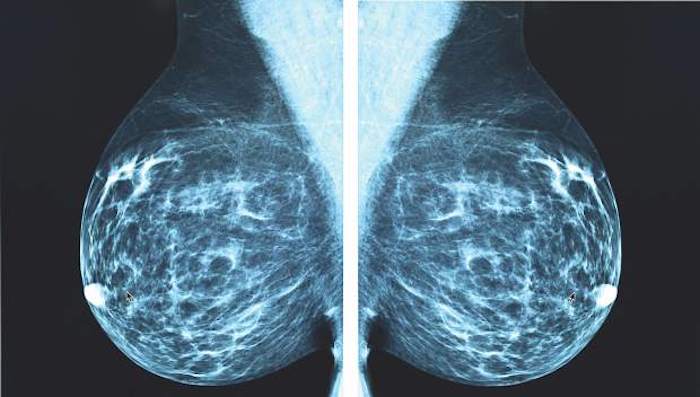

A growing body of research now suggests that x-ray mammography is accelerating the cancer epidemic in the western world.

In 2006, a paper published in the British Journal of Radiobiology, entitled “Enhanced biological effectiveness of low energy X-rays and implications for the UK breast screening programme,” revealed the type of radiation used in x-ray-based breast screenings is much more carcinogenic than previously thought:

Recent radiobiological studies have provided compelling evidence that the low energy X-rays as used in mammography are approximately four times – but possibly as much as six times – more effective in causing mutational damage than higher energy X-rays. Since current radiation risk estimates are based on the effects of high energy gamma radiation, this implies that the risks of radiation-induced breast cancers for mammography X-rays are underestimated by the same factor.

Greenmedinfo.com reports: In other words, the radiation risk model used to determine whether the benefit of breast screenings in asymptomatic women outweighs their harm, underestimates the risk of mammography-induced breast and related cancers by between 4-600%.

So, let’s assume that these reviews are correct, and at the very least, the screenings are not doing any good, and at worst, causing more harm than good. The salient question, however, is how muchmore harm than good? If we consider that, according to data from Journal of the National Cancer Institute (2011), a mammogram uses 4 mSv of radiation vs. the .02 mSv of your average chest x-ray (which is 200 times more radiation), and then, we factor in the 4-600% higher genotoxicity/carcinogenicity associated with the specific “low-energy” wavelengths used in mammography, it is highly possible that beyond the epidemic of over-diagnosis and over-treatment, mammograms are planting seeds of radiation-induced cancer within the breasts of millions of women.